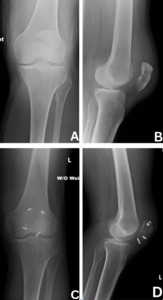

All patients were placed in the supine position with a tourniquet on the upper thigh, which was inflated prior to incision. An incision was made centered over the patella and dissection was carried down to the fracture site with care to avoid damage to the quadriceps and patellar tendons. After irrigation of the fragments, fluoroscopy was utilized to ensure proper reduction with clamps. Medial and lateral K-wires were then driven across the fracture in a perpendicular fashion (Figure 1). Proper placement was ensured via fluoroscopy. A small incision was then made through the quadriceps tendon to create room for a 3.5 mm cannulated overdrill along the K-wire. This step was repeated on the patellar tendon site. This allowed passage of our suture buttons (Arthrex TightRopeTM) through each drill hole with a suture passer. At this point, buttons were then present in all four quadrants of the patella (Figure 2). Minimal tensioning of the suture buttons was then performed.

Fluoroscopy was used to confirm appropriate reduction of the articular surface (Figure 5). The knee was then taken through range of motion to ensure there was no gapping while taking care not to compromise the repair. The wound was copiously irrigated and closed with close inspection of the retinaculum. If the retinaculum was disrupted, it was then repaired with a combination of SutureTape and Vicryl suture.